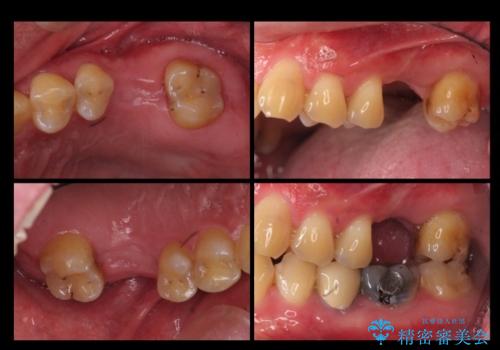

上の奥歯のインプラント、全体的な虫歯治療

- 上の奥歯が無いところにインプラントを希望して来院。

外国人の患者様で、複数の歯科に話を聞きに行ったとのことでした。

インプラントの向かい合わせの歯や隣の歯の虫歯治療も併せて行なっています。